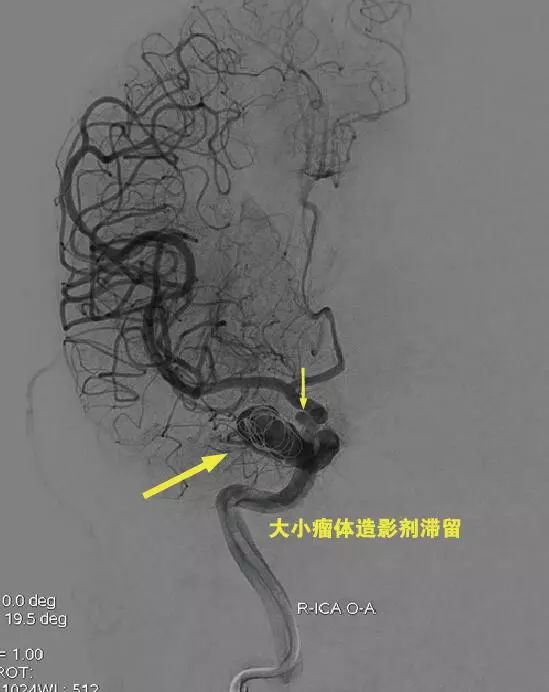

Tubridge血管重建装置4.0mm*35mm经T-track到位,锚定Tubridge头端,缓慢推送、释放Tubridge,“推支架、撤微导管张力”全程缓慢减张释放,支架尾端接近释放状态约2mm时,撤微导管T-track张力,支架弹开,近端贴壁。造影显示支架展开贴壁良好,动脉瘤内血流明显滞留。

用预留的微导管Ethelon10完成瘤内2枚弹簧圈填塞,因为AN位于硬膜环以外,床突段,瘤颈不算太大,仅“稀疏填塞”。术后即刻效果显著,瘤内血栓形成,分支血管通畅。